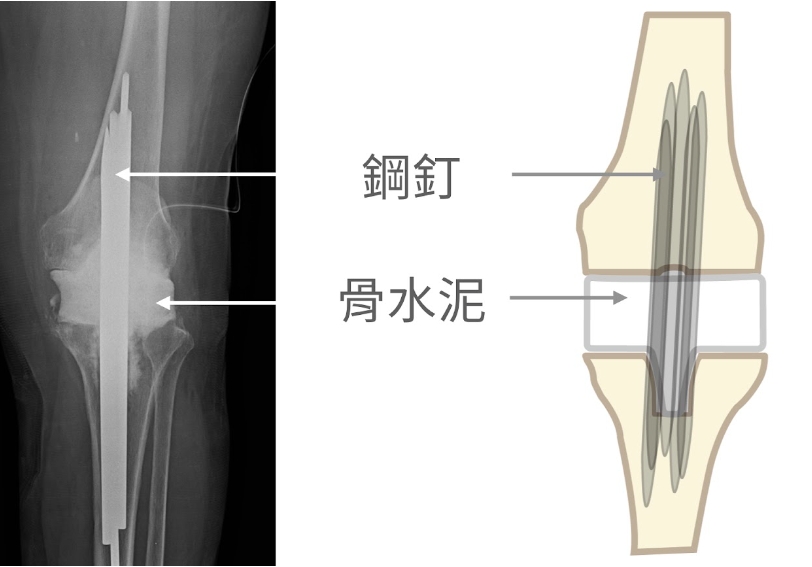

第二階段:待感染控制後,重新裝置人工關節

拔除人工關節,置放含抗生素的骨水泥假體術後 X 光片

重新裝置人工關節術後 X 光片